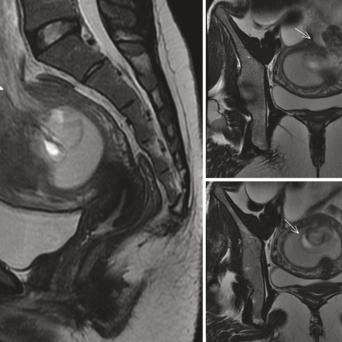

L’image

du jour

Illustration.